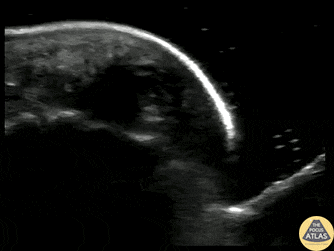

40s M who works as a carpenter presented with finger pain and swelling 10 days after he injured his finger when a heavy object fell on it. He sought medical care on the day of the injury and had radiographs which were negative for fracture, and there was no visible wound initially. On this visit, he was noted to have focal erythema and edema to his distal phalanx. POCUS was performed to evaluate for abscess and flexor tenosynovitis. To improve visualization, a water bath was used. The finger tip is shown here, with a small circumscribed area of hypoechoic fluid at the distal phalanx, indicative of a felon. Incision and drainage was performed and the patient was discharged on oral antibiotics and with plan for PCP follow up. Nayun Lee, MS3 Dr. Molly Thiessen Denver Health Medical Center